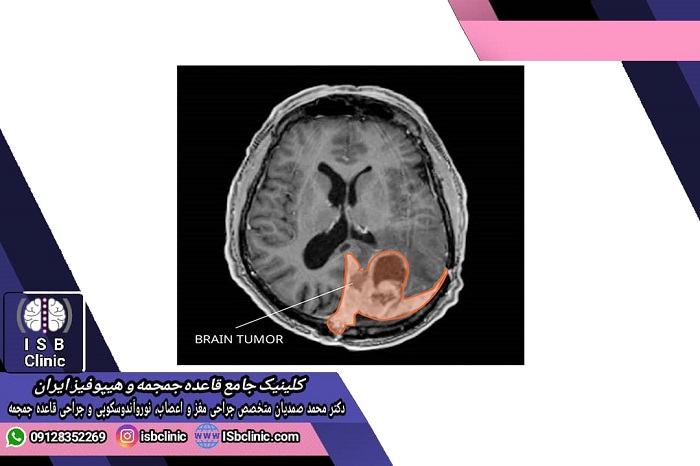

آزمایشات تصویربرداری MRIو سی تی اسکن : تصویر برداری ام آر آی با استفاده از ایجاد میدان مغناطیسی ، تصاویر مختلفی از ابعاد و زوایای مختلف مغز ثبت می کند که به تشخیص دقیق محل و ابعاد تومور کمک می کند. در مقابل، آزمایش سی تی اسکن با استفاده از پرتوهای اشعه ایکس انجام می شود و تصویری مقطعی از بافت مغز نشان می دهد. گاهی برای تشخیص بهتر بافت سرطانی، ممکن است از مواد کنتراست که در برابر اشعه های تابیده شده واکنش نشان می دهند استفاده شود.